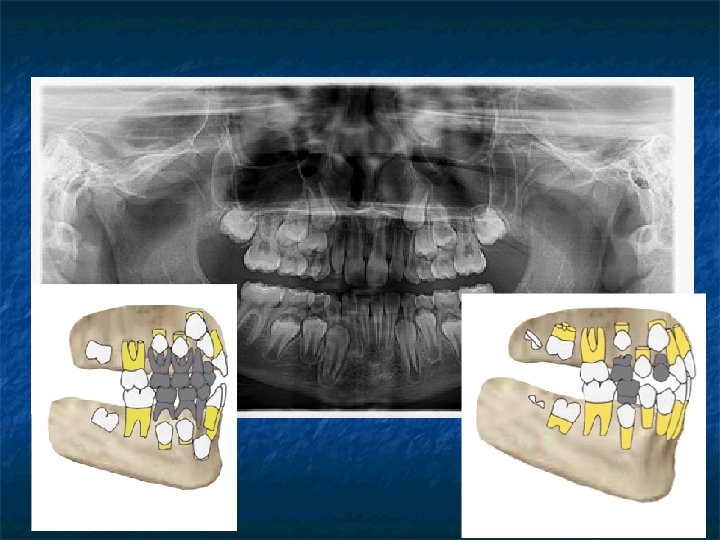

Adli Dişhekiminin Kimlik Tespitinde Yararlandığı Özellikler: n n n n n Dişler, Dental kayıtlar, Radyografiler, Dental fotoğraflar, Dental modeller, Diş ve damak ve ısırık izleri, Vücut izleri, Restorasyon ve protezler, Tükürük.

Adli Dişhekiminin Kimlik Tespitinde Yararlandığı Özellikler: n Radyografi ve dental fotoğraflar

Adli Dişhekiminin Kimlik Tespitinde Yararlandığı Özellikler: n Dental modellerin incelenmesi